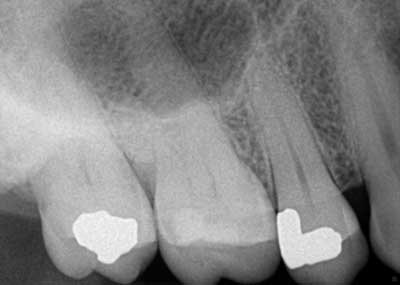

Such is the case for the patient who presented with a chief complaint of biting and occasional slight cold sensitivity on his upper right back molar (No. 2). The patient stated that it hurt to chew and that he wanted to get his tooth fixed as soon as possible. Upon radiographical examination, the periapical for No. 2 was normal. Clinically, the tooth presented with a conservative occlusal amalgam with caries distal to the restoration. In addition, a fracture line on the mesial and distal marginal ridges was noted. Percussion and cold testing were normal and periodontally, the tooth was stable. Bite assessment with the tooth sleuth revealed a positive response on the lingual cusp when biting and releasing. Diagnosis: reversible pulpitis secondary to a crack.

Due to the separation of the buccal and lingual cusps, a crown was recommended to restore the tooth to full form and function. In addition, the patient was informed that the fracture line likely extended further than the naked eye could observe; excavation of the tooth would reveal more detail. (1)

At the crown appointment, the amalgam filling and compromised mesial and distal marginal ridges were removed. The fracture line was indeed detected and noted to extend across the floor in a mesial/distal fashion.Fig. 3